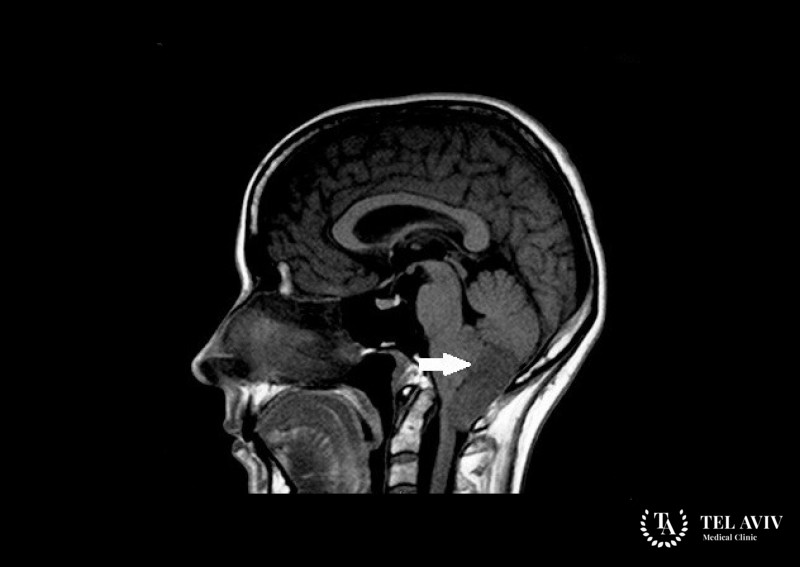

Если изучение истории болезни и симптоматика дают врачу подозрения на злокачественную опухоль в центральной нервной системе, то пациенту назначаются диагностические исследования. Наиболее эффективными методами диагностики рака головного мозга являются компьютерная томография и МРТ. С учетом быстрого роста опухоли и ее агрессивности, диагностировать ее, как правило, не составляет опытному специалисту никакого труда.